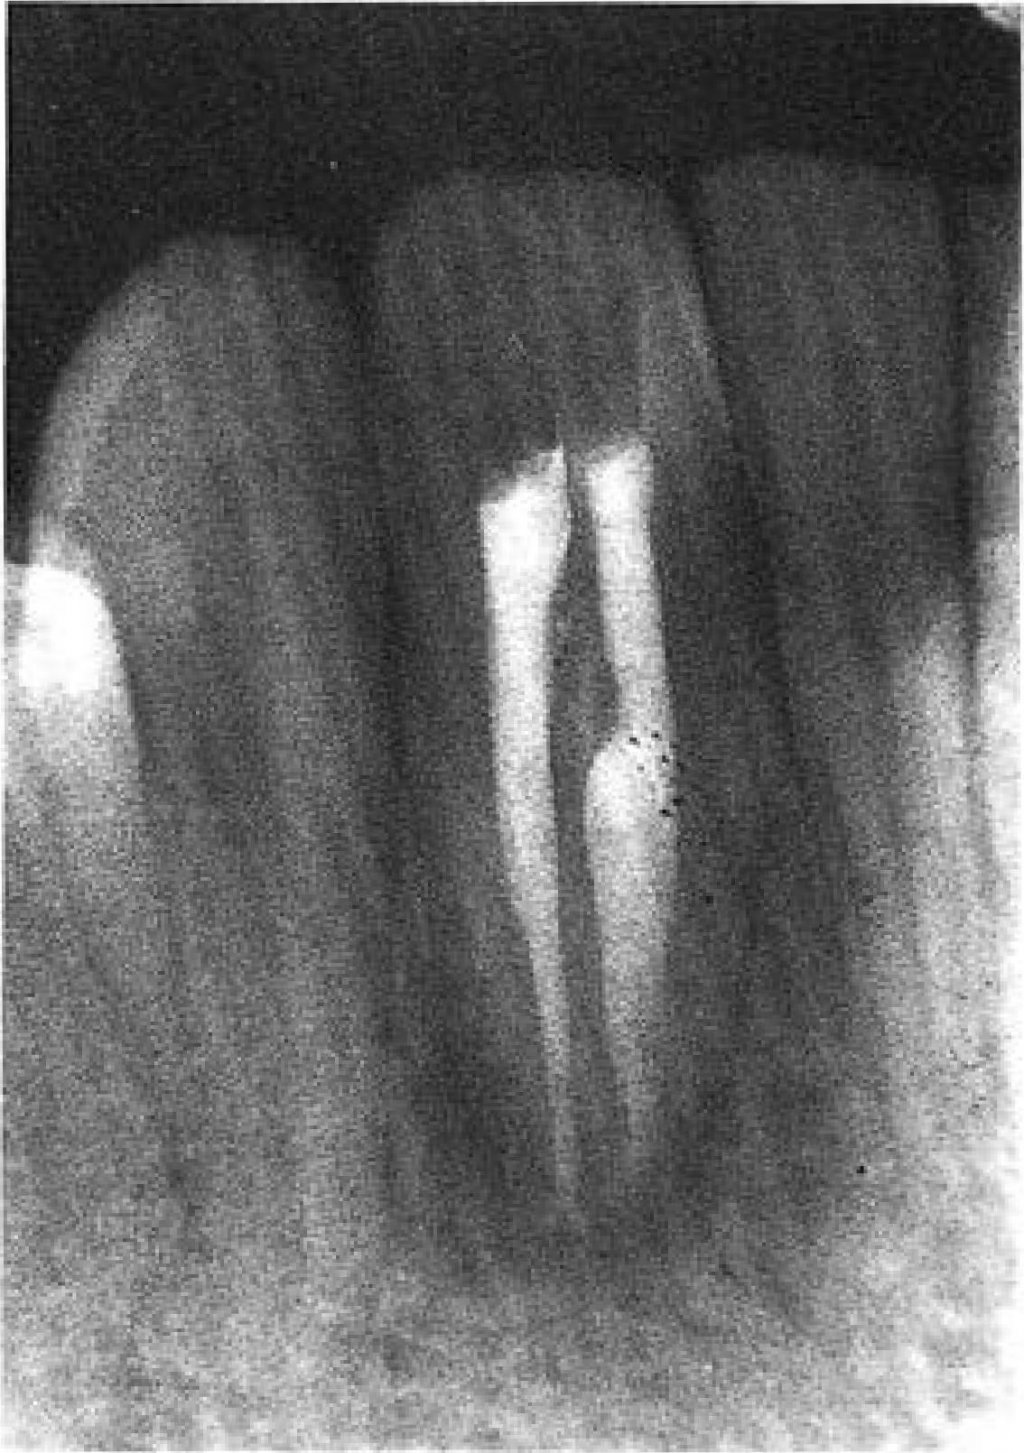

A 25-year-old Greek male complaining of acute pain in the right mandibular lateral incisor (42) was referred to the Endodontic Clinic at the University of Athens. The patient's medical and dental history was uncomplicated. The clinical examination showed that the tooth was tender to percussion and palpation, but free of decay, Pulp sensitivity tests (thermal and electrical) were negative. There was no history of trauma and the patient had no harmful habits. The crown of tooth 42 was wider than that of the left mandibular lateral incisor (32). In the labial surface of the crown, there was a groove, and in the lingual, a pit. The colour of the tooth did not differ from the adjacent teeth and the total number of teeth in the arch was normal (Figs 1 & 2). Radiographic examination revealed that the tooth had a single broad root with two separate root canals. ln the mescal pulp cavity, there was a dens invaginatus extending through the root and opening in the apical region. In the periapical region, there was a radiolucency (Fig. 3).

The patient returned after 3 months, and canals were obturated with Grossman's sealer and gutta-percha using the lateral condensation technique in the distal canal and vertical condensation of warm gutta-percha in the mesial canal, the latter in an attempt to fill possible irregularities in this canal space. There did not appear to be any communication with the distal root canal (Fig. 4).

One year post-operatively, the patient remained asymptomatic and there was radiographic evidence or periapical healing (Fig. 5).